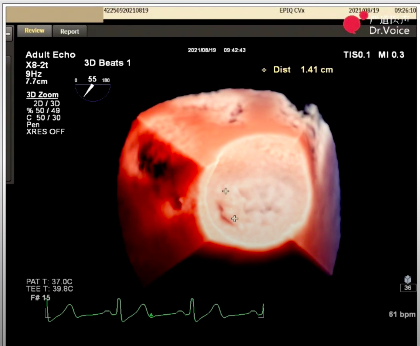

1、手术团队使用MitraClip®独特的三层双调弯导管,经股静脉穿刺,在食道超声引导下完成房间隔穿刺。穿刺后将导管送入左心房,靠近二尖瓣目标位置。术中TEE三维超声可明确显示瓣膜脱垂区域,脱垂区域主要位于二尖瓣前叶A1区及前交界,且面积较大,显著增加手术难度。

三维超声显示瓣膜脱垂区域